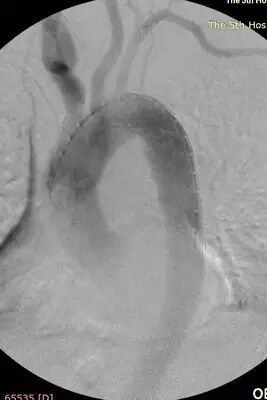

但术前的CTA评估又发现新的问题(图1、2),患者同时合并左侧锁骨下动脉的重度狭窄,狭窄>80%,平素血压多测量右上肢,并未发现,入院测量双上肢血压差别高达30mmHg!更困难的是,主动脉溃疡的破口位于胸10椎体部位,行覆膜支架腔内治疗,患者术后截瘫风险较大。患者病情危重,一旦主动脉破裂出血,死亡率极高!患者家属再次陷入恐慌,在此两难之际,王兵教授果断决策,手术要做,且决定同时介入治疗锁骨下动脉狭窄,因为锁骨下动脉狭窄的解除不仅能改善患者脑部及上肢供血,同时对脊髓供血起到良好的代偿作用,但即便如此,术前也与麻醉科胡强夫主任反复沟通,做好脑脊液穿刺引流准备,最大限度降低截瘫风险。

图1:左侧锁骨下动脉重度狭窄

充分的术前评估及准备,确保了手术的顺利进行。术中王兵教授亲自主刀,崔文军副主任及王颖、司江涛主治医师作为助手,经股动脉小切口,先于左侧锁骨下动脉狭窄处准确定位后置入球扩支架1枚,再次造影明确溃疡位置后,将主动脉带膜支架顺利输送到位,并成功释放,完全覆盖病变主动脉,复查造影效果满意(图3)。术后患者即清醒,安全返回病房,测量双上肢血压无差别,双下肢温度、颜色正常,感觉及运动均无异常,即挽救了患者生命,也成功避免了截瘫的发生,大家悬着的心都放了下来。术后施敏护士长带领的护理团队,娴熟而全面的护理确保患者平稳度过围手术期,术后10天复查CTA:左侧锁骨下动脉及主动脉支架均位置良好,形态满意。目前李大娘已顺利康复出院。